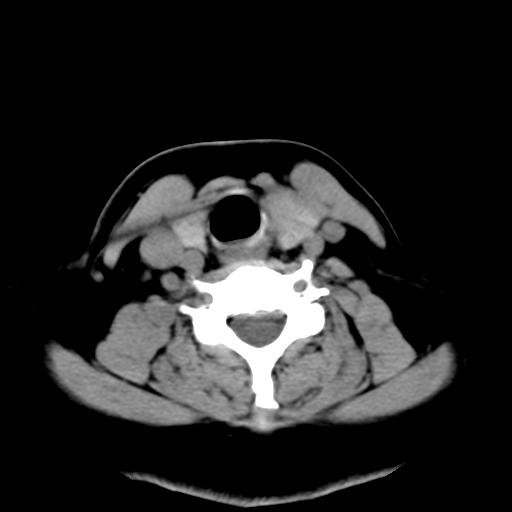

标题: CT25491:女,55岁,发现左侧甲状腺肿块一个月。 [打印本页]

标题: CT25491:女,55岁,发现左侧甲状腺肿块一个月。

女,55岁,发现左侧甲状腺肿块一个月,彩超示:甲状腺多发结节伴左叶结节液化。